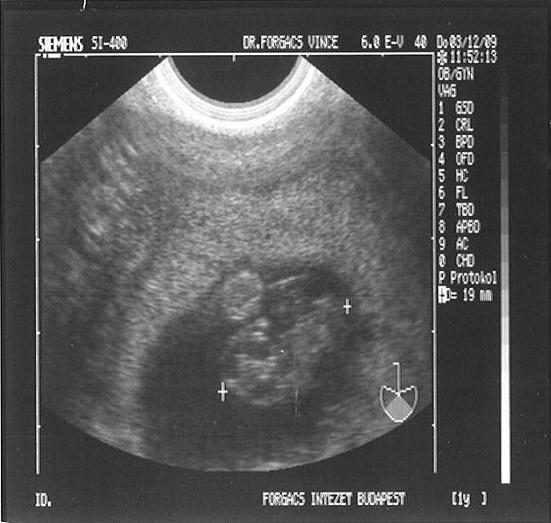

Nekünk is Ő nézte meg Marcit, amikor kiderült a ciszta, és nagyon alapos, megnyugtató volt.